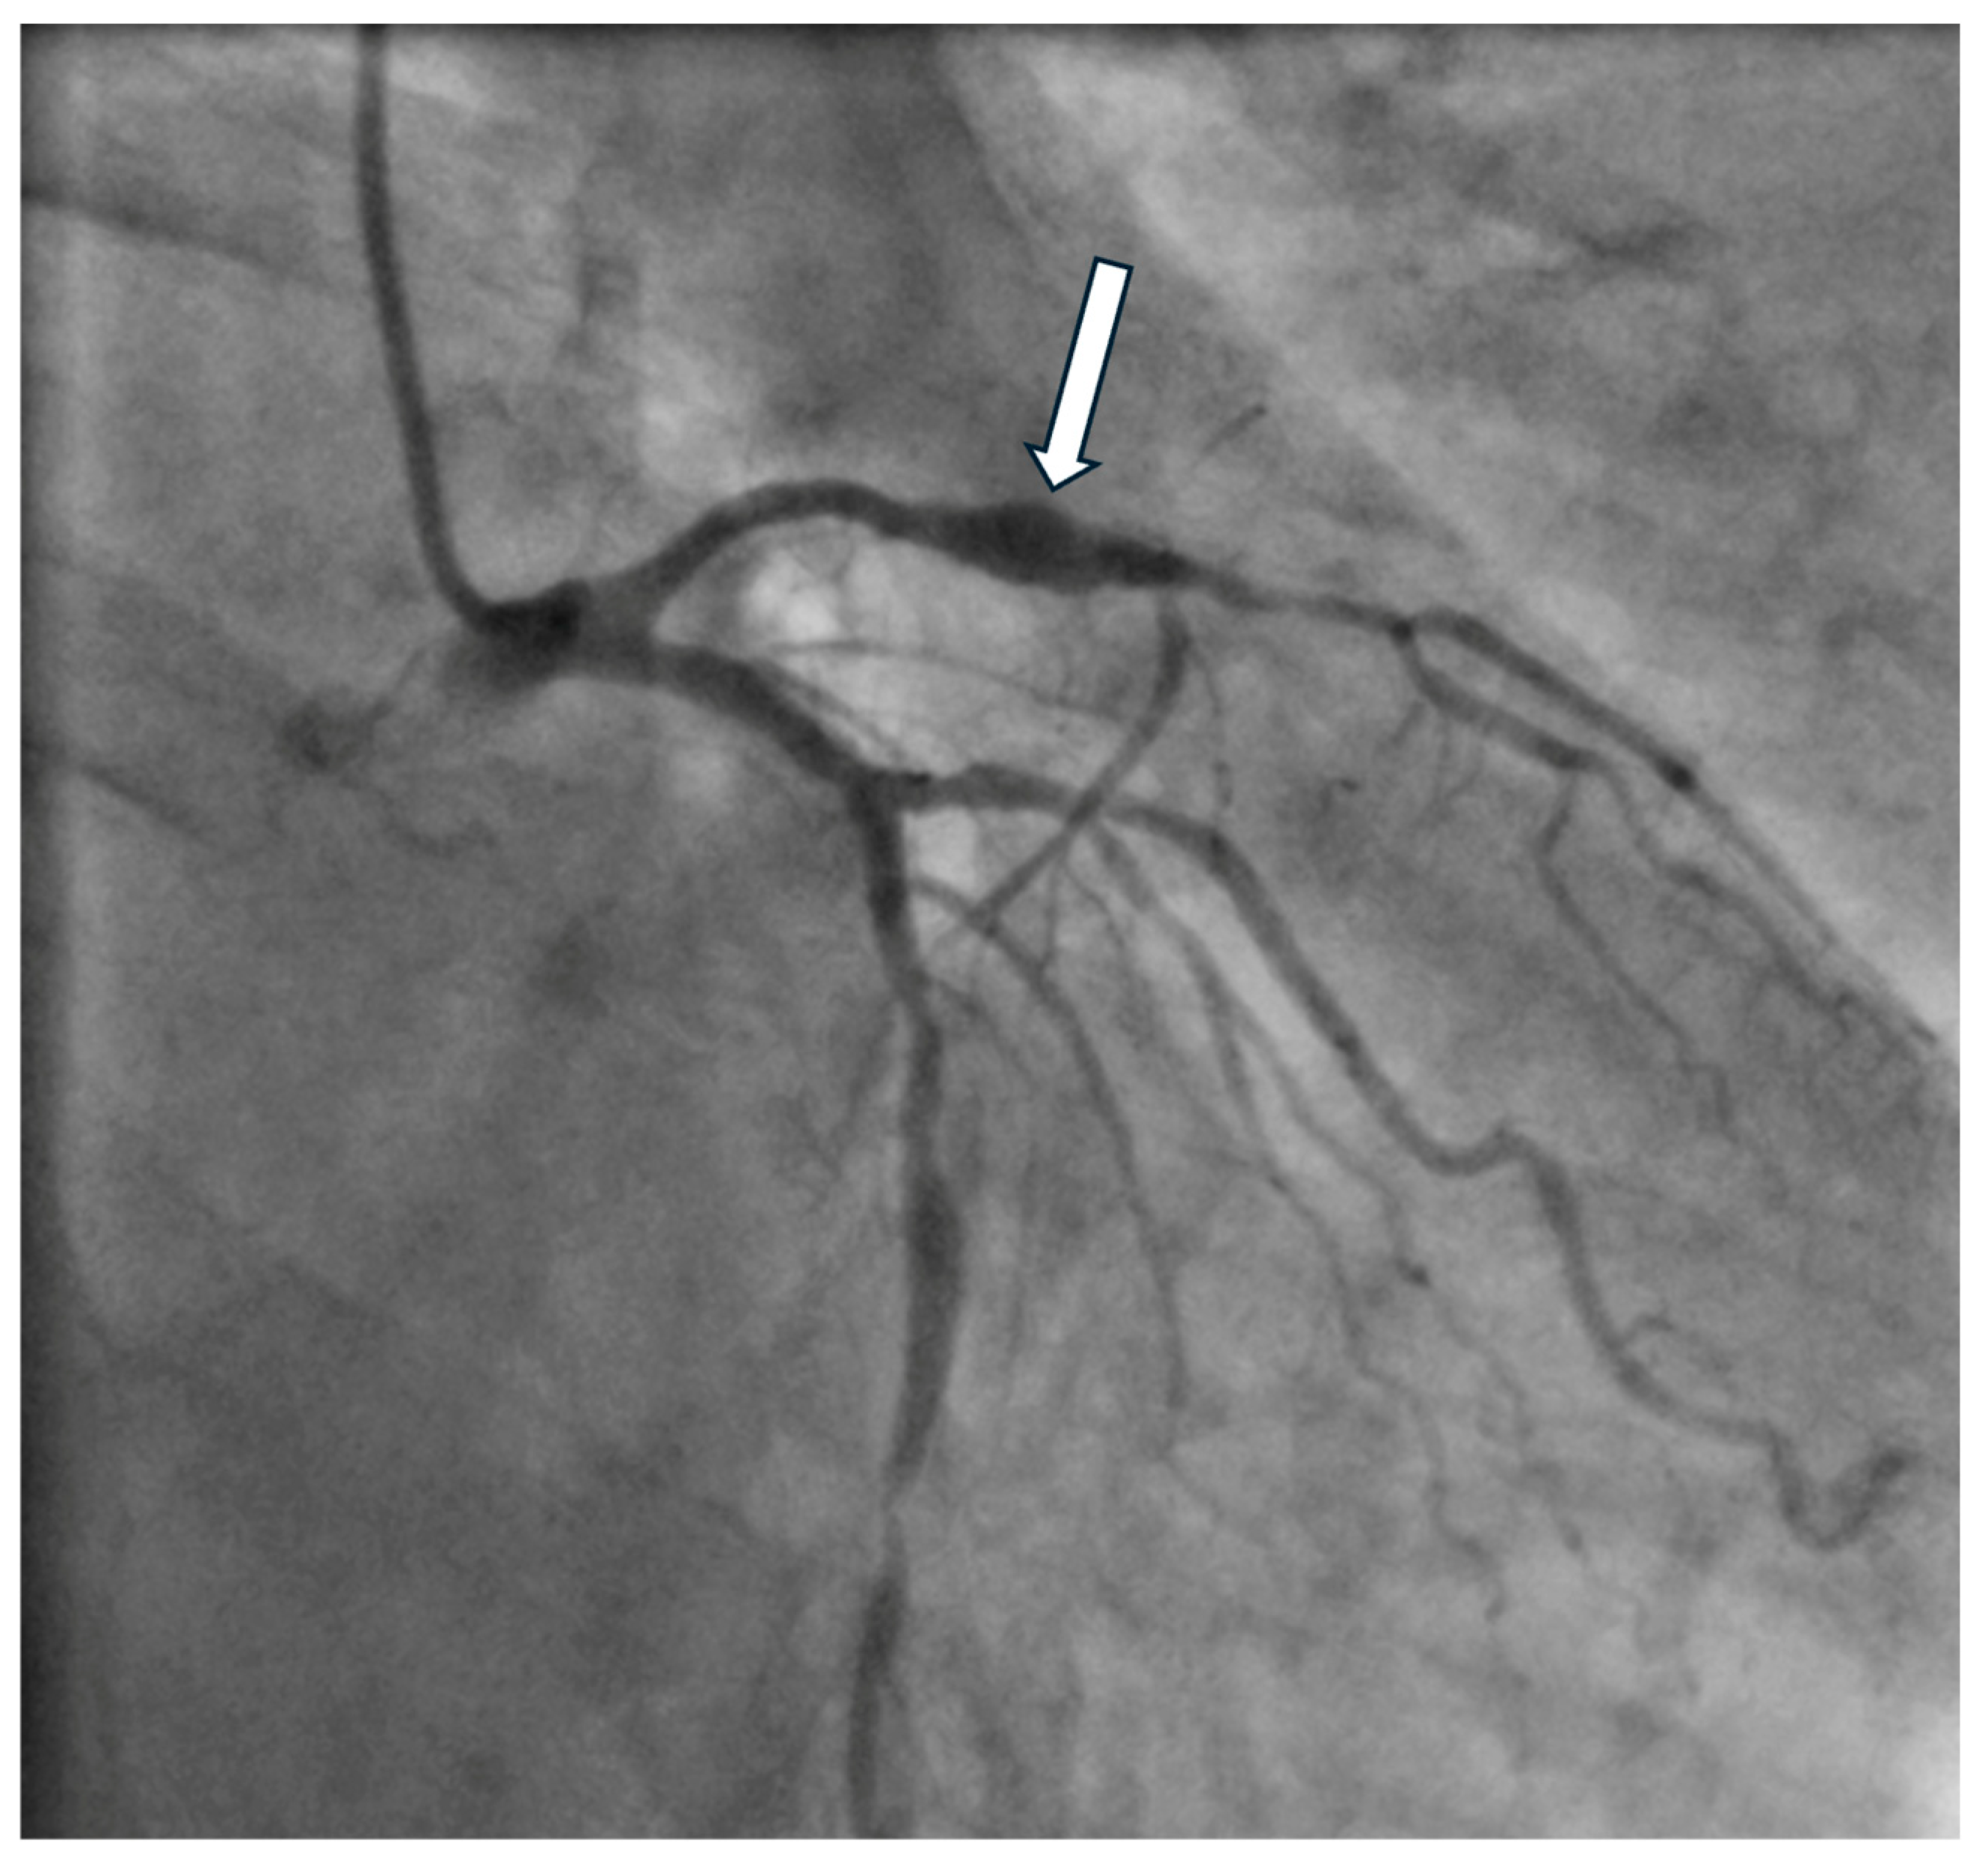

4. Diagnostics

7. Prognosis